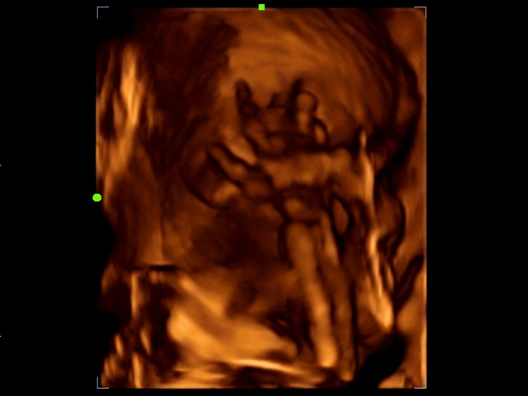

Клинические изображения

- NTE (компрессионная эластография), поддержка исследований с контрастом и широкий выбор опций для акушерства/гинекологии, в том числе в режиме 3D/4D.

- Smart Face – эксклюзивная опция в этом классе аппаратов! (автоматически убирает артефакты перед лицом плода).

Система в большей степени предназначена для общих исследований, но также поддерживает объемные датчики и 3D/4D опции для визуализации плода.